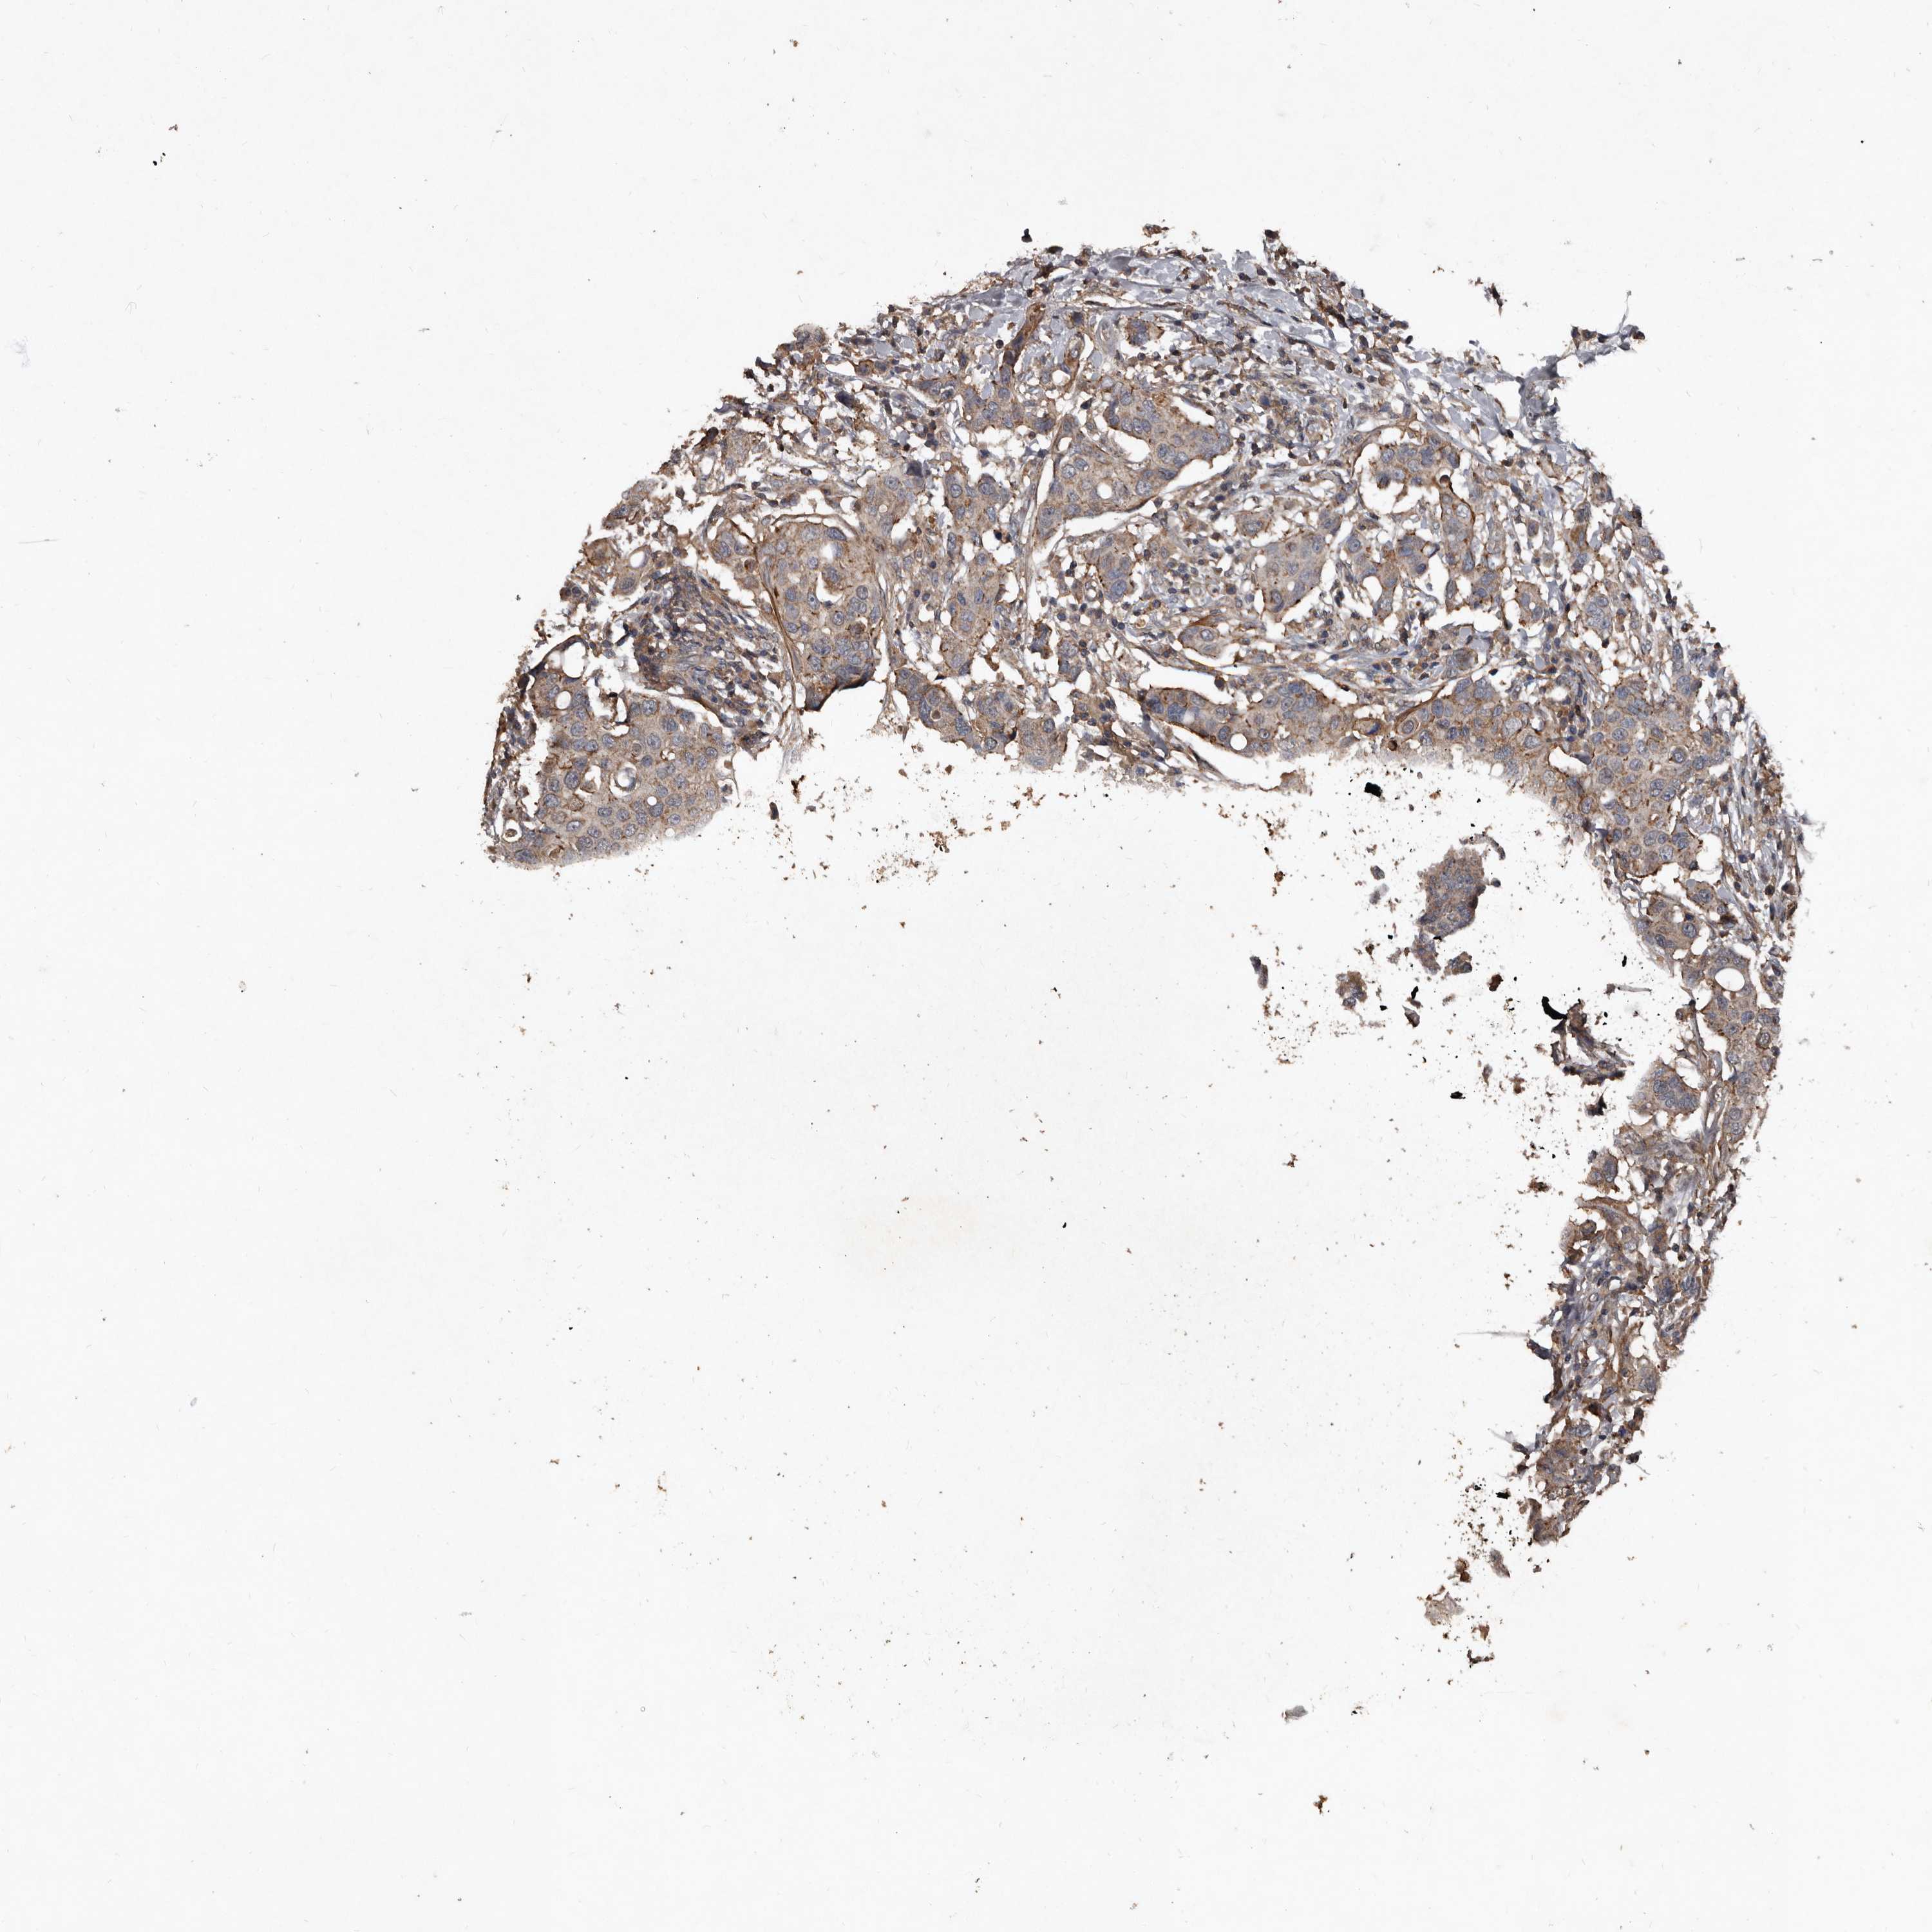

CANCER BREAST CANCER Show tissue menu

BRCA TCGA BRCA VALIDATION PROTEIN EXPRESSION